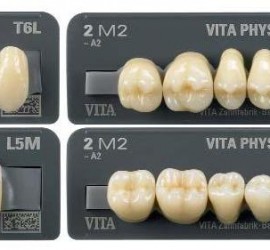

Жевательная проба. Критерий оценки эффективности работы жевательного аппарата, которую определяют по 3 показателям: жевательная эффективность, жевательный эффект и жевательная способность. Тестовым материалом для жевательной пробы могут служить пищевые продукты (орехи, морковь, хлеб) и искусственно созданные (20% желатина, отвержденная в 4% формалине, ортосил, другие пластмассы). Обязательным условием для воспроизводимости результатов пробы […]